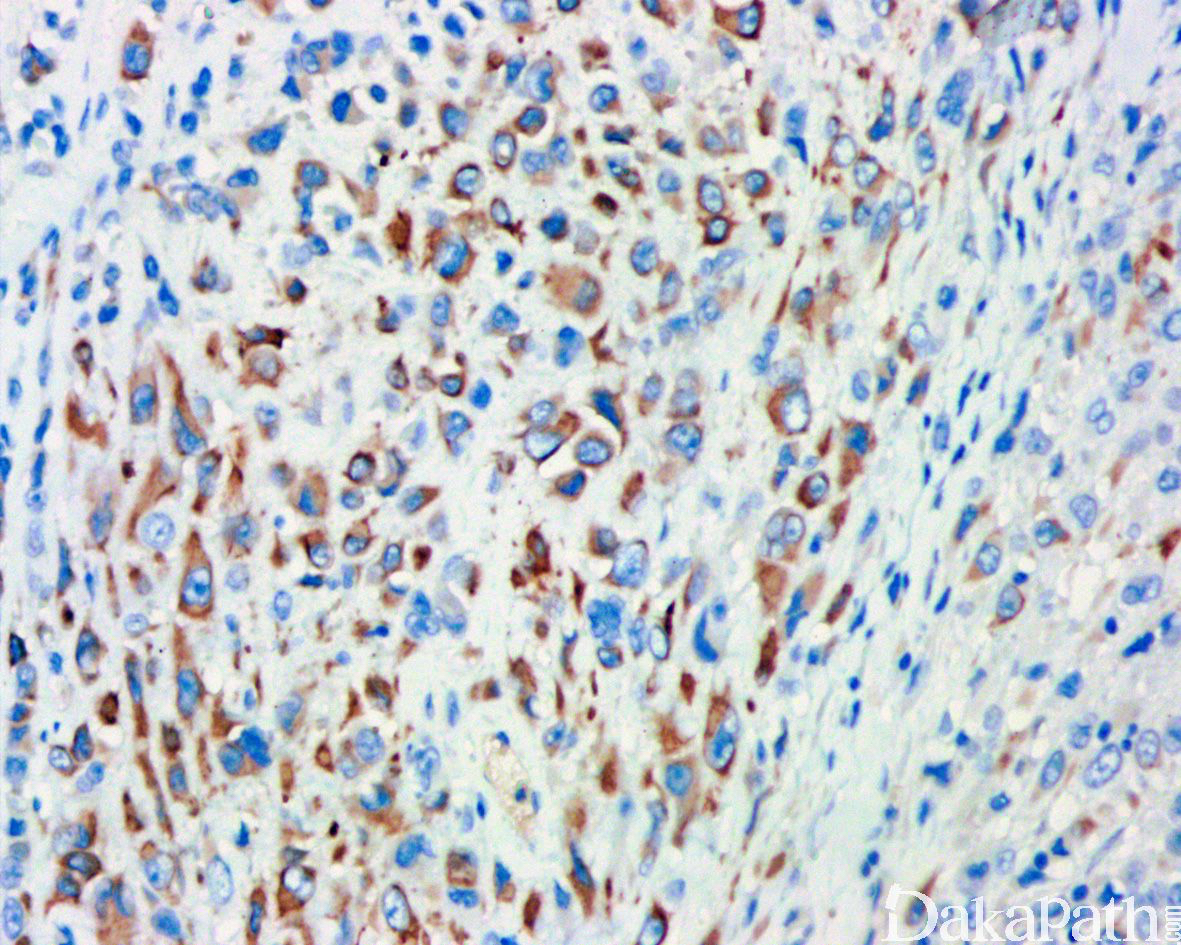

免疫组织化学染色:

瘤细胞 AE1/AE3. EMA、CK8. CK19 和 vimentin 常阳性,50%-70%病例 CD34 阳性,95%以上显示 SMARCB1(INI1)表达丢失;部分病例可表达 MSA、α-SMA、S-100. ERG 和 NSE,偶尔表达 SALL4,—般不表达 CK20. desmin、NF、CEA 和 CD31。